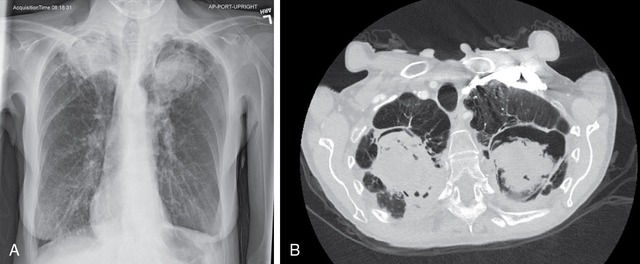

Việc chẩn đoán nhiễm nấm nội tạng đòi hỏi sự kết hợp giữa lâm sàng, xét nghiệm và hình ảnh học. Cấy máu và các mẫu dịch bệnh lý vẫn là phương pháp truyền thống, nhưng thời gian chờ kết quả lâu và độ nhạy chưa cao. Các xét nghiệm hiện đại như phát hiện kháng nguyên hoặc marker sinh học trong máu, PCR tìm DNA nấm, cùng chụp CT ngực để phát hiện tổn thương điển hình của aspergillosis, đang ngày càng đóng vai trò quan trọng giúp phát hiện sớm.

Hình ảnh CT ngực cho thấy tổn thương phổi điển hình do nấm Aspergillus ở người già.